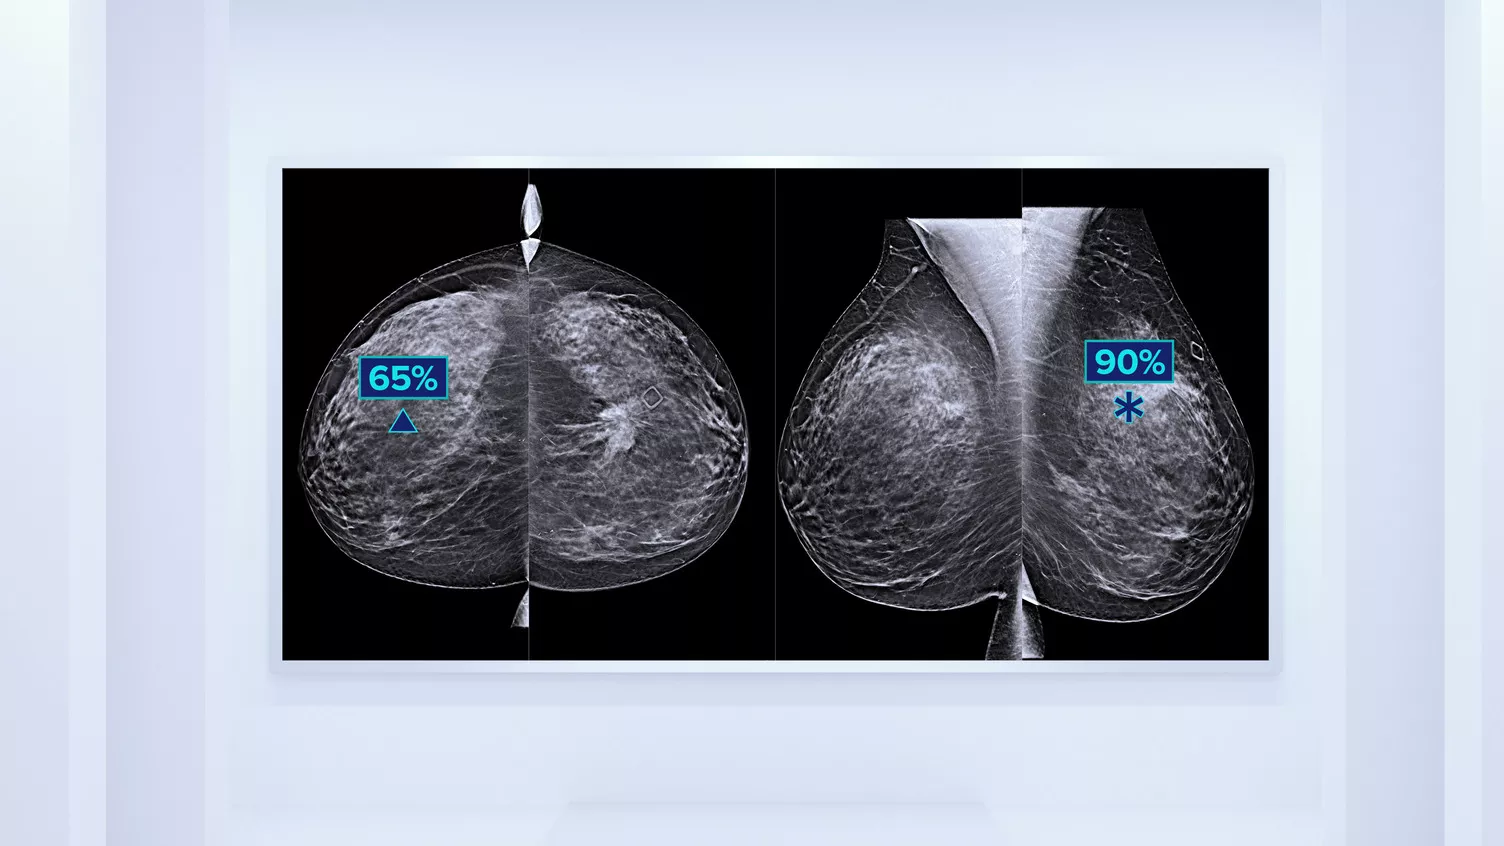

In addition to volume, pattern and texture of fibroglandular tissue may play just as an important role in mammographic cancer risk prediction.3-5 By analysing and categorising breast texture and pattern, our technology can deliver the accurate information you need to achieve more consistent and reliable scoring and confidently design patient-specific screening.

Objective machine learning algorithm that assigns breast density category based on analysis of breast tissue texture and patterns.